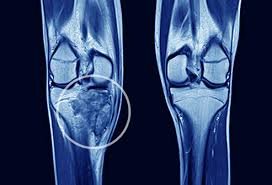

makanan sehat bagi pejuang kanker tulang

Menjalani pengobatan kanker tulang bukanlah hal yang mudah untuk dilakukan tentunya para pejuang kanker tulang perlu asupan nutrisi yang tepat untuk mendukung kekuatan tubuh, mempercepat pemulihan, serta meningkatkan kualitas hidup secara keseluruhan.